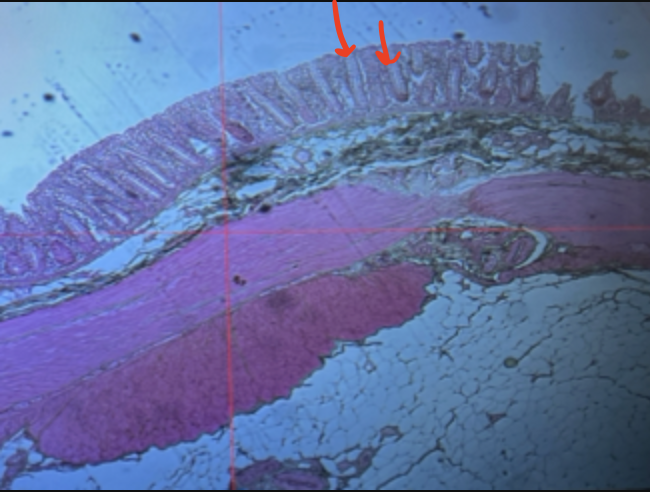

jejunum

villi

intestinal crypts

lumen

mucosa

mucosal epithelium

lamina propria

muscularis mucosa

submucosa

muscularis (externa)

serosa/adventitia